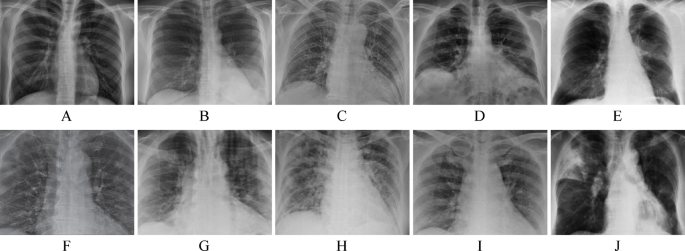

In segmentation experiments using 10 X-ray images and 10 breast cancer images, the primary objective was to demonstrate that the GBJAYA could achieve superior segmentation results and exhibit strong adaptability acrossdifferent threshold levels. GBJAYA was compared with 10 other similar peers at both low threshold levels (4, 5, 6) and high threshold levels (12, 16, 20). In these experiments, two publicly available medical image datasets were used for validation. The first is the COVID-19 chest X-ray dataset, constructed by Cohen et al.25, which contains 679 frontal-view and 82 lateral-view images from patients in various clinical conditions. This dataset is widely used for lung region segmentation and disease-assisted diagnosis. The second is a breast cancer histopathological image dataset from Databiox, consisting of 922 H&E-stained tissue slice images, annotated according to three IDC (Invasive Ductal Carcinoma) grading standards26. It includes multiple magnification levels and rich structural details, making it suitable for multi-threshold segmentation of tissue regions. These two datasets represent radiological and histological imaging tasks, respectively, and provide a comprehensive basis for evaluating the adaptability of the proposed algorithm. The lung X-ray images are labeled as A to J in Fig. 2, and the breast cancer images are labeled as K to T in Fig. 3. Since the proposed multi-threshold segmentation operates in the grayscale domain, each RGB image was converted to grayscale using MATLAB’s rgb2gray(∙) function. This function applies a weighted combination of the R, G, and B channels, ensuring consistency with the 2D histogram-based thresholding framework adopted in our method. The population size for all segmentation methods was set to 20, and to minimize randomness, each test was independently conducted 30 times. The experimental results were evaluated using PSNR27, SSIM28, and FSIM29, with the evaluation results compared using mean, standard deviation, the Wilcoxon signed-rank test10, and the Freidman test11. It is important to note that the proposed GBJAYA-based multi-threshold segmentation is designed as a pre-processing or enhancement technique, rather than a full instance segmentation method. The goal is to highlight regional contrast and delineate coarse structural zones in a fully unsupervised manner, which can serve as an input or initialization for downstream biomedical image analysis tasks such as instance segmentation or classification. Detailed analysis of the experimental results confirmed that GBJAYA demonstrated excellent segmentation performance and strong adaptability across various threshold levels in multi-threshold image segmentation.

Representative COVID-19 lung X-ray image used as input for segmentation (not the output)25.